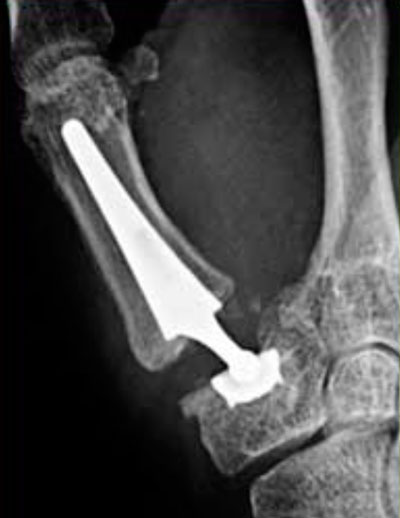

3ª) Colocación de una prótesis trapecio metacarpiana.

Prótesis trapeciometacarpiana. Tratamiento 3.

Imagen de prótesis trapeciometacarpiana. Tratamiento 3.